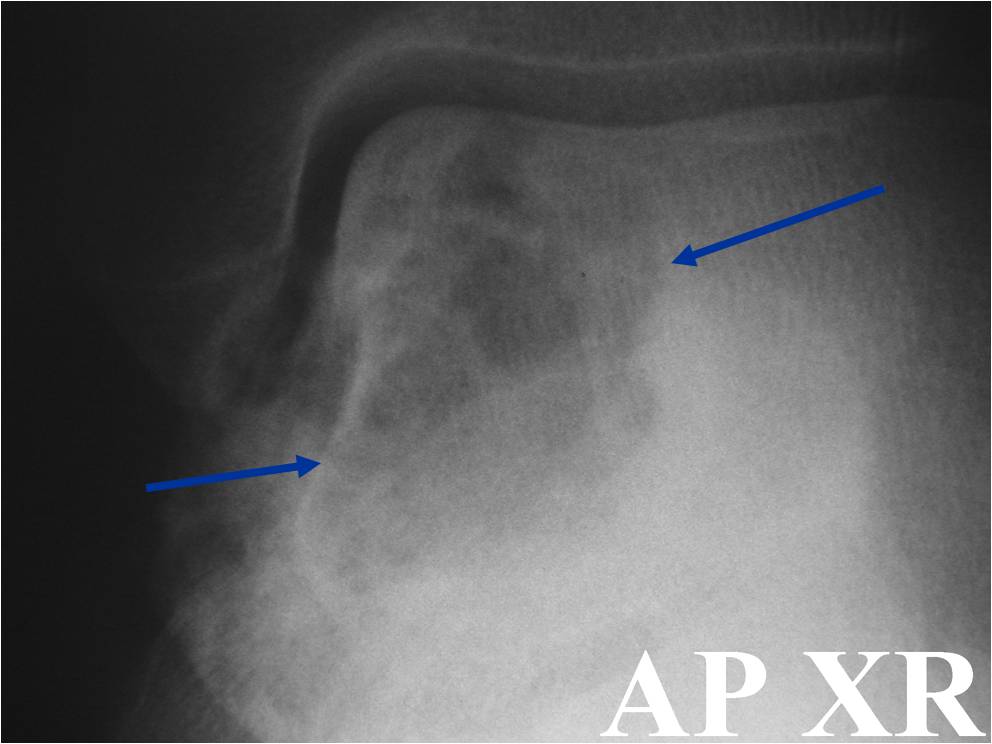

General Information Enchondroma is a benign indolent intramedullary hyaline cartilage neoplasm Accounts for 10% of all benign osseous tumors Limited growth, most lesions are less than 5 cm in maximal dimension Bones grow from a cartilaginous growth plate that...